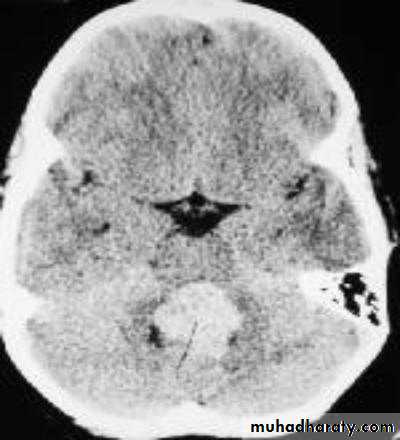

• Computed Tomography scan (CT scan) with/without contrast• Magnetic Resonance Imaging (MRI) with/without contrast